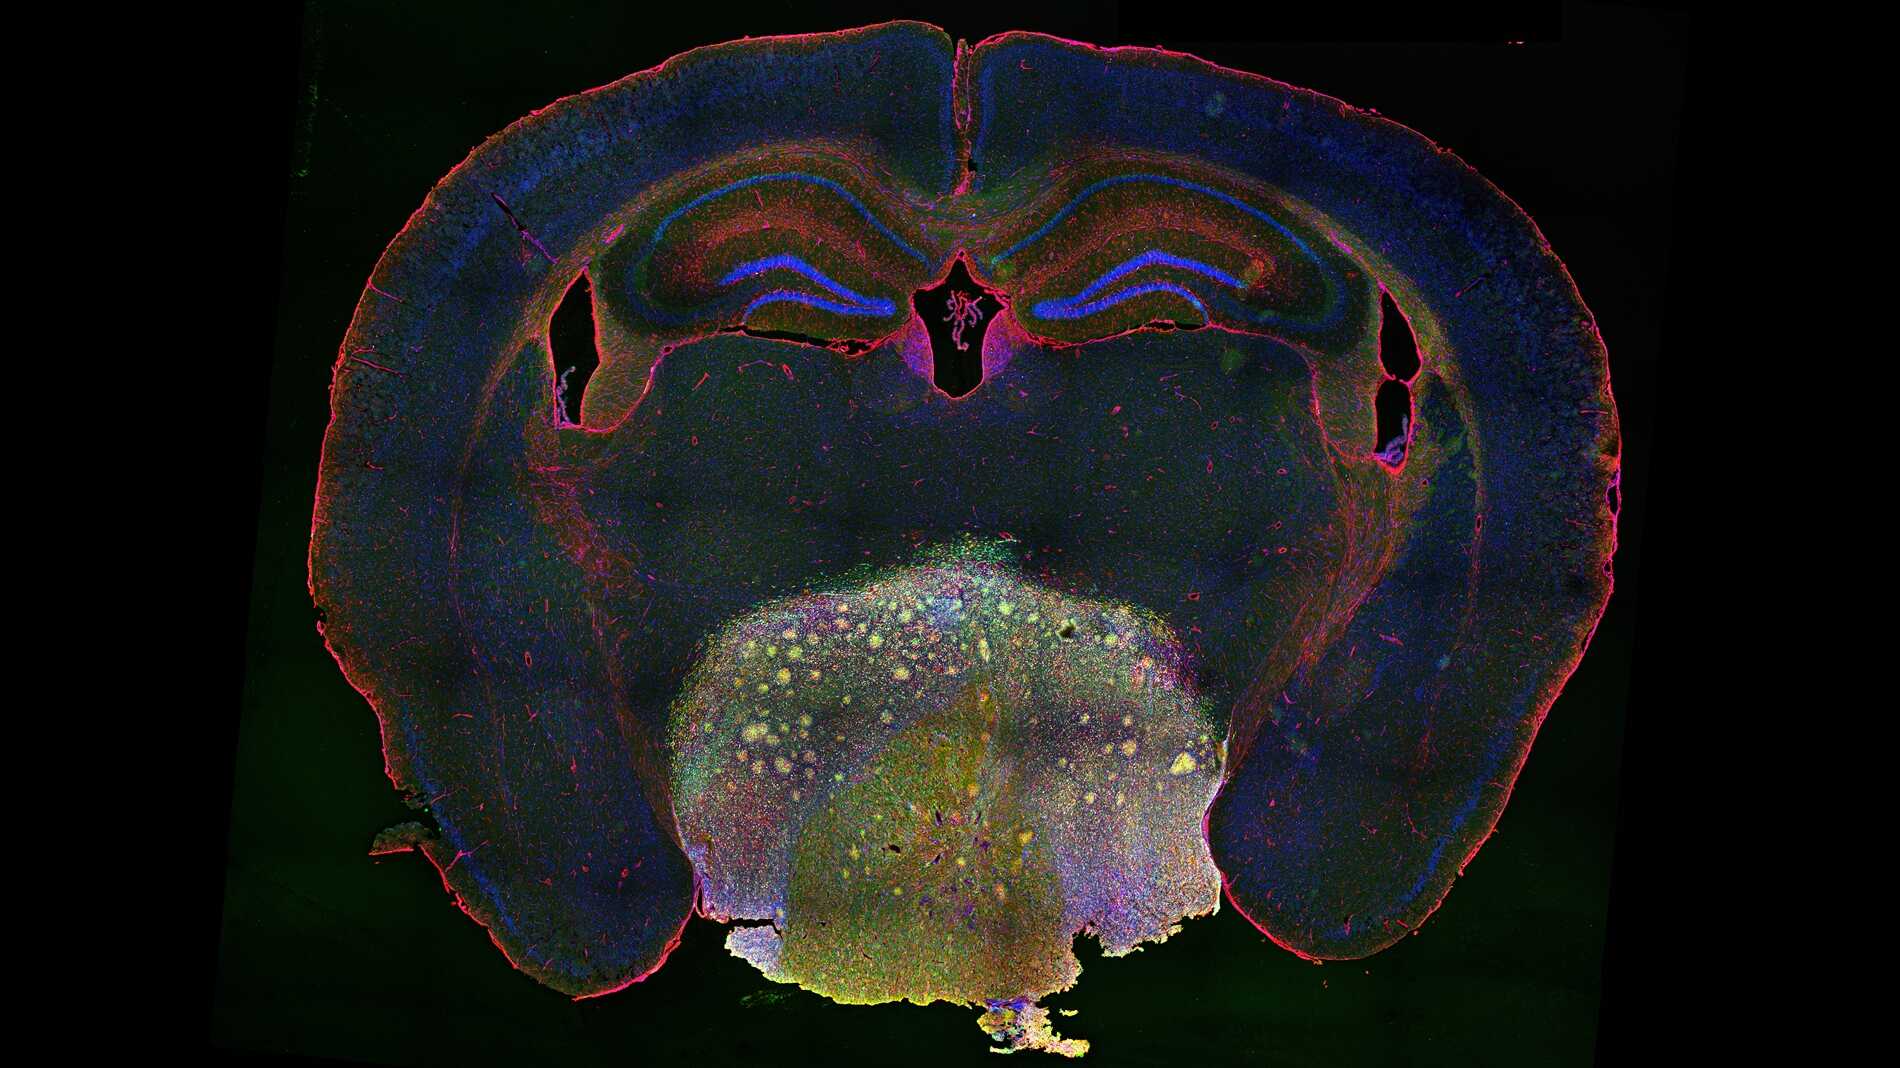

Researchers Unlock Craniopharyngioma Growth Mechanism and Identify Potential New Therapy

Researchers from Professor WU Qingfeng’s lab at the Institute of Genetics and Developmental Biology of the Chinese Academy of Sciences, identified a promising targeted therapy for craniopharyngioma through advanced animal modeling and high throughput drug screening.